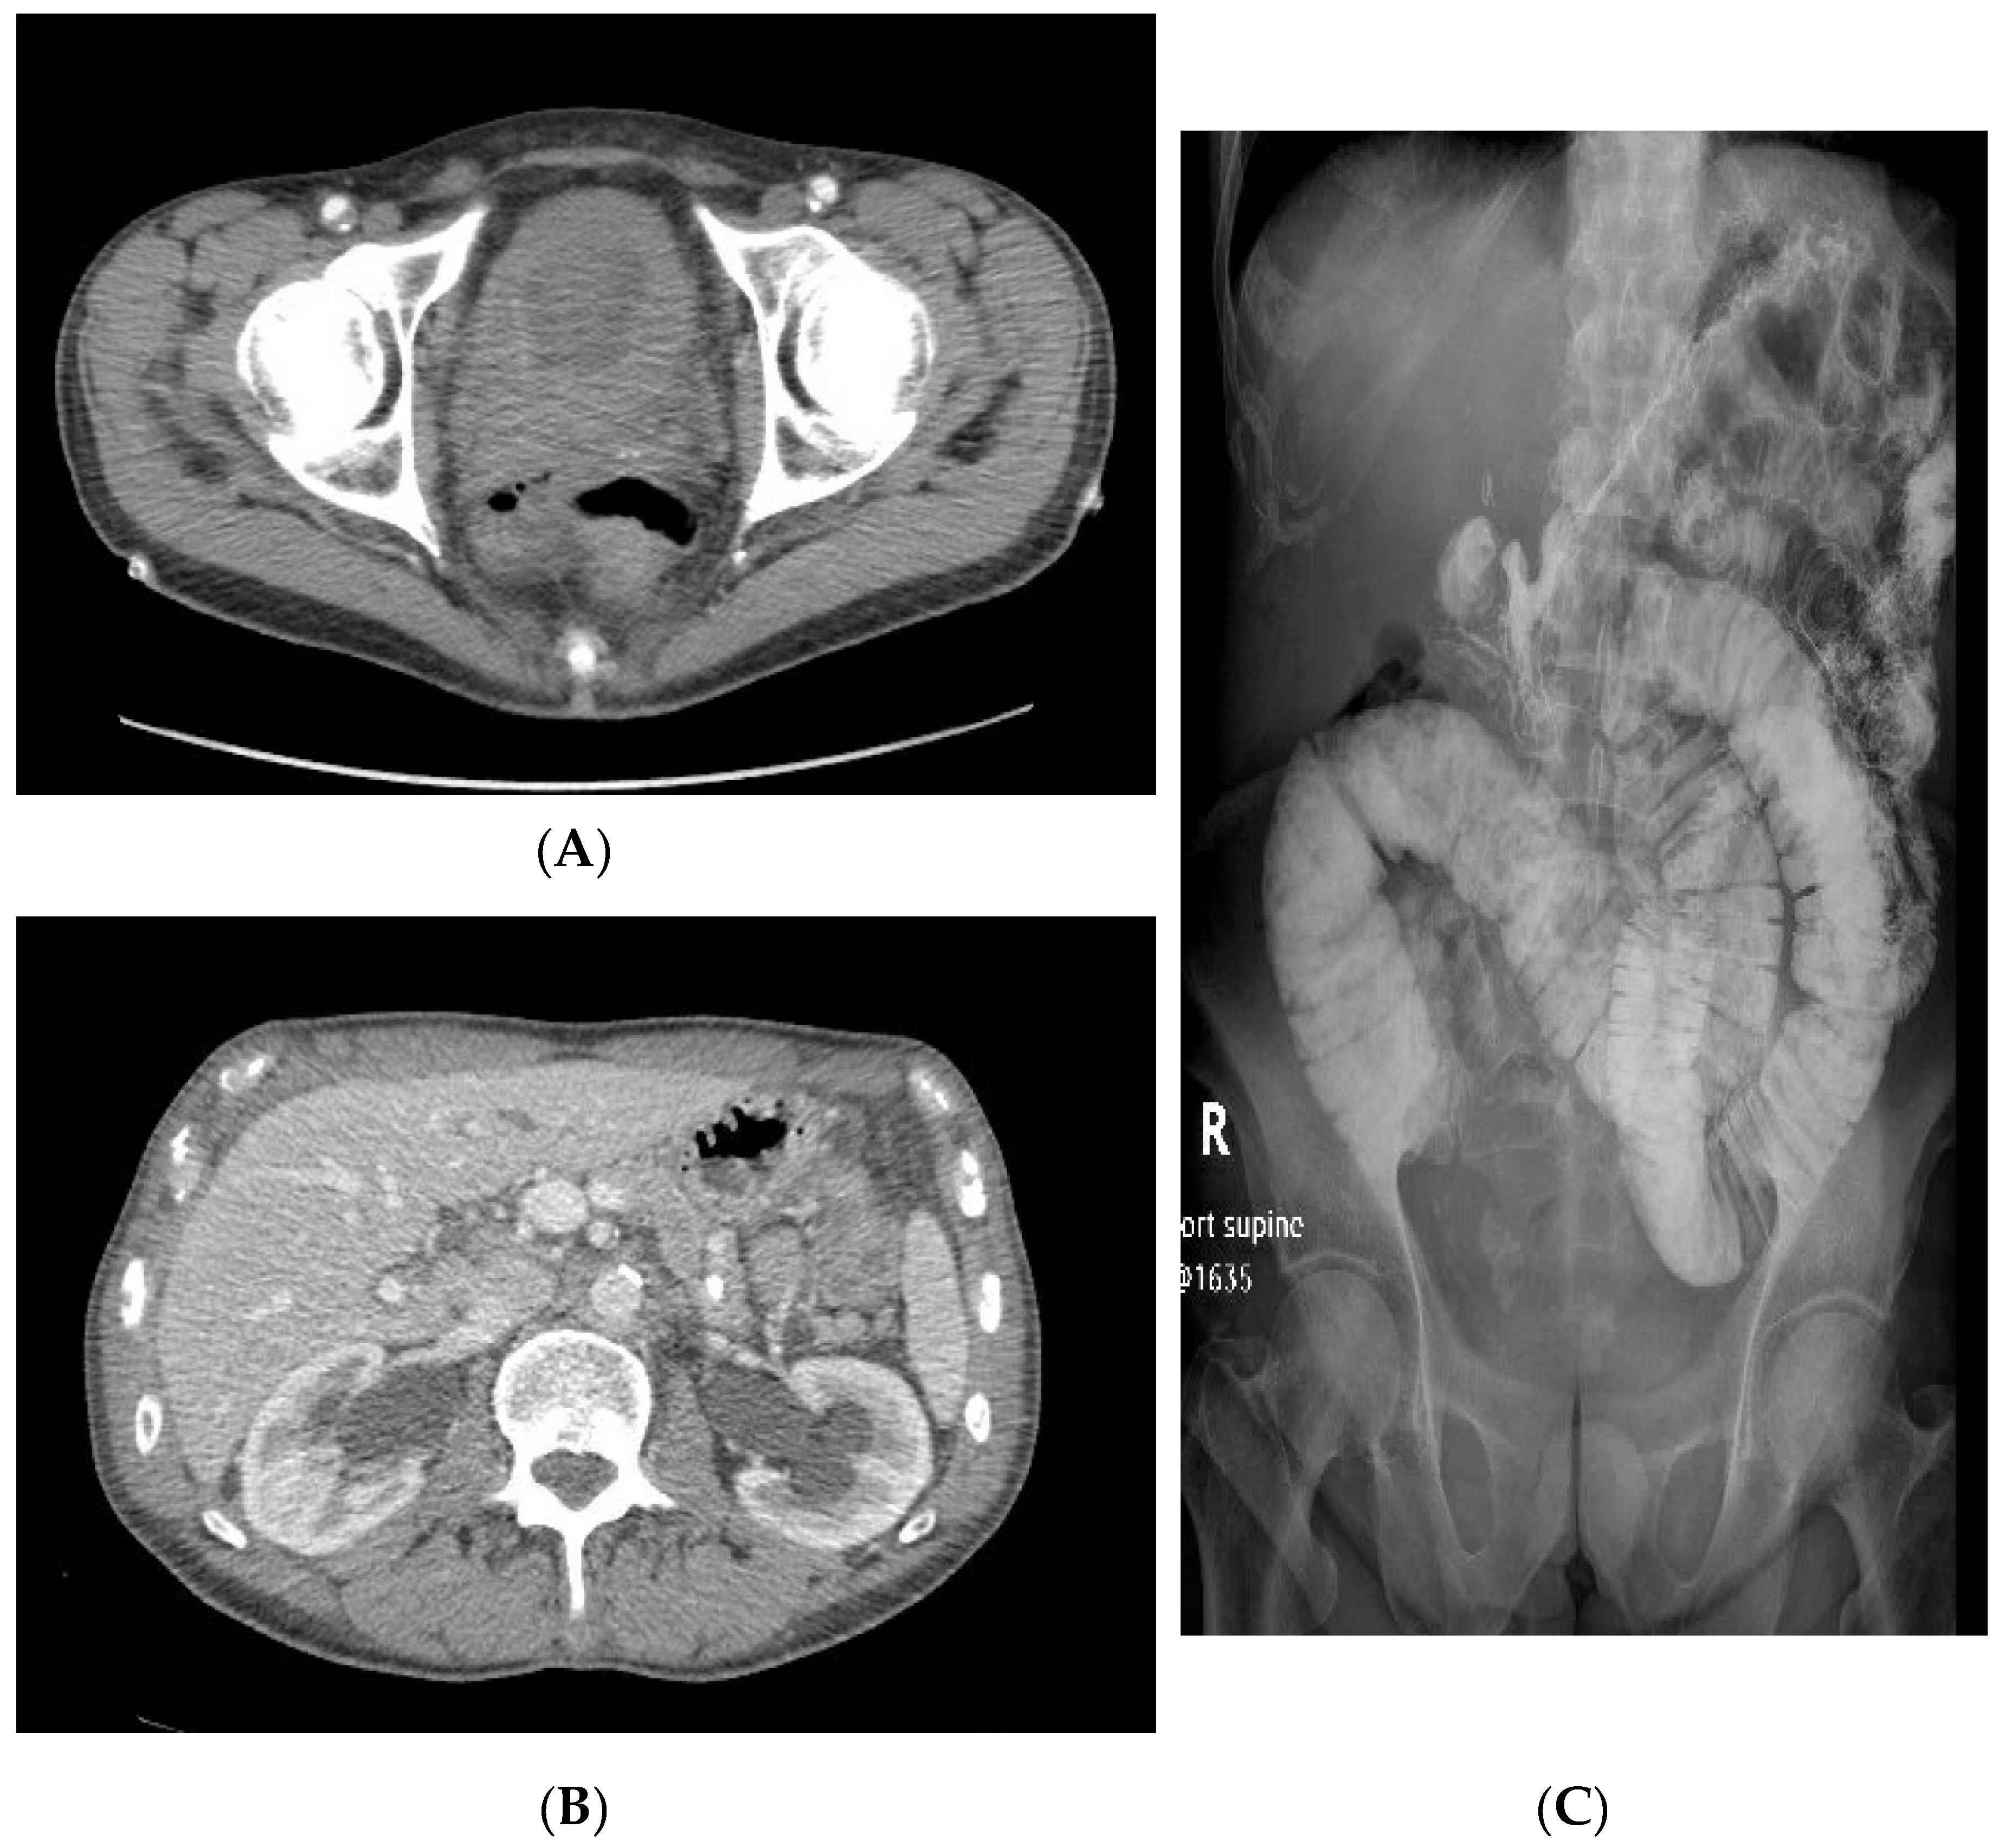

Figure 2.

CT scan showing bilateral hydronephrosis. (A) CT scan pre-cystectomy showing bladder thickening; (B) CT scan shows bilateral hydronephrosis; (C) Small bowel follow-through showing dilated small bowel loops, contrast ends before cecum, polypoid filling defects suggest stool in the small bowel.

A 61-year-old Caucasian male presented with dysuria, with a 40-pack-years of smoking history, coronary artery disease, hypertension, and chronic gastroparesis. However, given symptoms of increased pelvic pain, urinary urgency, and hematuria, a cystoscopy was performed and showed a bladder tumor that was treated with primary transurethral resection of bladder tumor (TURBT). The pathology revealed high-grade PVUC invading the lamina propria and muscularis propria with viable cells in both layers (Figure 1). After also experiencing flank pain, an ultrasound and a CT scan were performed, revealing bilateral hydronephrosis for which nephrostomy tubes were placed and bladder wall thickening, increased renal echogenicity, and seminal vesicle calcifications were found (Figure 2). He completed three cycles of neoadjuvant dose-dense methotrexate, vinblastine, doxorubicin, and cisplatin (dd-MVAC), which was complicated by multiple gastrointestinal (GI) symptoms of nausea, vomiting, resultant hypokalemia, and cytopenia, but he was able to successfully undergo definitive robot-assisted laparoscopic radical cystoprostatectomy, bilateral lymph node dissection with bilateral ureterolysis, and neobladder continent urinary diversion with ileum. The final pathology revealed ypT2N0Mx PVUC bladder cancer. While the resolution of bilateral hydronephrosis was seen initially, he developed persistent GI symptoms ten months later that warranted an eventual cholecystectomy. Regardless, symptoms of nausea, vomiting, and pain persisted, which necessitated obtaining a CT scan that showed changes that included recurrent bilateral hydronephrosis and bowel loop thickenings suggestive of the development of enteritis; a small bowel follow-through revealed intestinal obstruction (Figure 3C). A surgical exploratory laparotomy revealed multiple tumor deposits, and a thick, fibrous, mass-like tissue adhering the transverse colon to the anterior abdominal wall was dissected. However, given the extent of the adhesions and tumor deposits occurring diffusely in the abdomen and pelvis, it was elected to not remove the affected small bowel and instead bring up an end-ileostomy to relieve his obstruction. The pathology from these biopsies showed metastases of the high-grade PVUC with infiltrating plasmacytoid and signet ring cells in the small bowel and omentum with immunostaining positive for GATA-3, CD138, CK20, and CK7 (Figure 3).